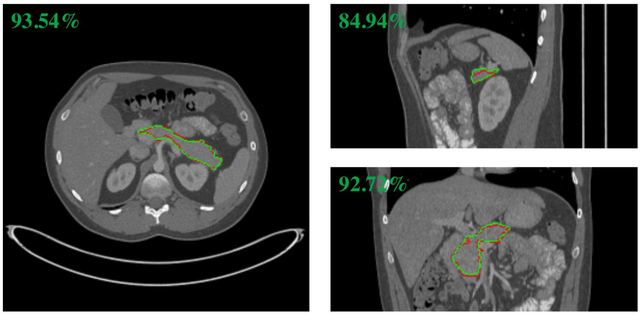

Recently 3D volumetric organ segmentation attracts much research interest in medical image analysis due to its significance in com- puter aided diagnosis. This paper aims to address the pancreas segmen- tation task in 3D computed tomography volumes. We propose a novel end-to-end network, Globally Guided Progressive Fusion Network, as an effective and efficient solution to volumetric segmentation, which involves both global features and complicated 3D geometric information. A pro- gressive fusion network is devised to extract 3D information from a mod- erate number of neighboring slices and predict a probability map for the segmentation of each slice. An independent branch for excavating global features from downsampled slices is further integrated into the network. Extensive experimental results demonstrate that our method achieves state-of-the-art performance on two pancreas datasets.